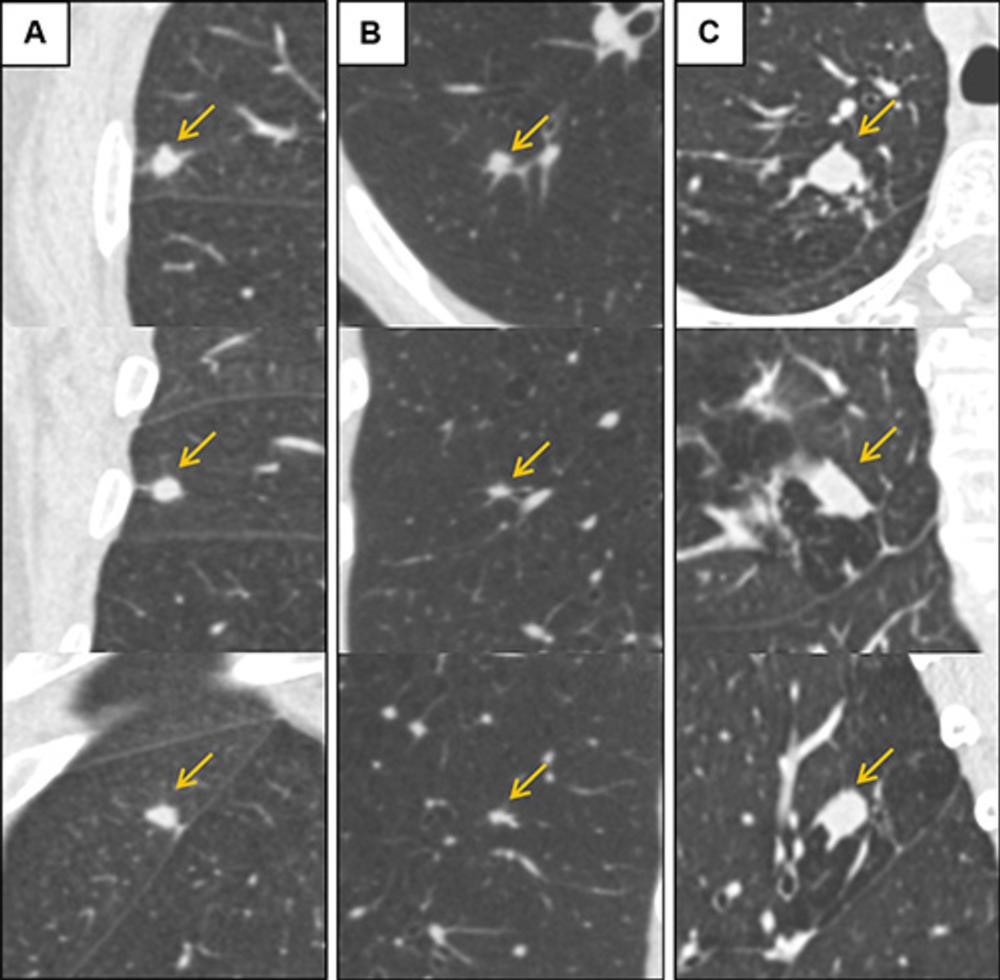

Figure 4. Low-dose CT images show examples of screen-detected pulmonary nodules (arrows) where the deep learning algorithm provides a more accurate malignancy risk estimation than the Pan-Canadian Early Detection of Lung Cancer (PanCan) model on axial (top), coronal (middle), and sagittal (bottom) planes. (A) Image shows a 9.7-mm malignant nodule (arrows) with a high deep learning risk score (32.3%) and low PanCan risk score (3.2%) in a 74-year-old male participant diagnosed with squamous cell carcinoma. (B) Image shows a 6.8-mm malignant nodule (arrows) with a high deep learning risk score (15.9%) and low PanCan risk score (1.2%) in a 71-year-old male participant diagnosed with adenocarcinoma. (C) Image shows a 19- mm benign nodule (arrows) with a low deep learning risk score (4.7%) and high PanCan risk score (32.7%) in a 50-year-old female participant. Additional PanCan input features used in the model were retrieved from original trial records, as follows: (A) negative for family history of lung cancer, negative for emphysema, negative for spiculation, negative for upper lobe location, nodule count: four; (B) negative for family history of lung cancer, negative for emphysema, negative for spiculation, negative for upper lobe location, nodule count: two; (C) negative for family history of lung cancer, positive for emphysema, negative for spiculation, positive for upper lobe location, nodule count: one.